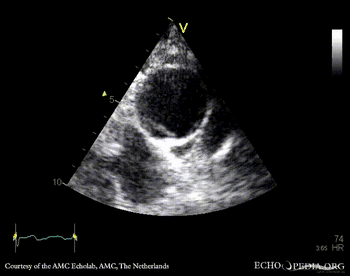

Aortic dissection type A

PSAX A5CH: dilated aortic root, dissection flap in ascending aorta